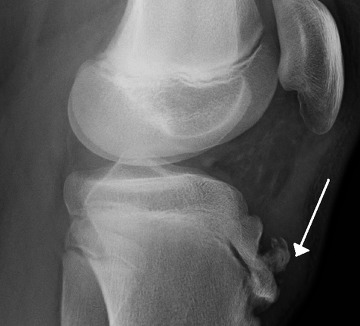

X-ray 검사를 합니다. 성장단계에 따라 크기는 다르지만 경골조면 즉 무릎의 바로 아래에 국한된 골단핵 변화, 유리골편이라는 것이 보여집니다. MRI검사를 하면 연골부를 덮고 있는 슬개건이 두꺼워져 있거나 주변 염증성 변화를 확인할 수 있습니다. 초음파로도 돌출된 뼈와 인대 비후도 볼 수 있습니다.